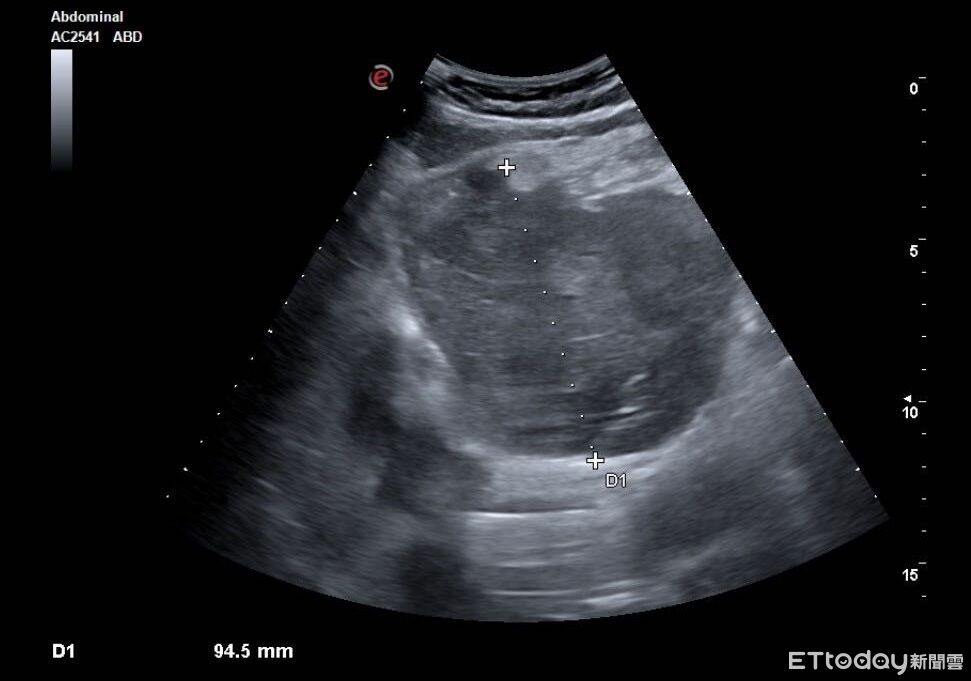

▲老伯肝臟有顆9公分巨瘤,恐是肝癌。(示意圖/CFP)

許多人一出現上腹痛,直覺反應就是「胃不舒服」,以為吃點藥就會好,但這可能是身體發出的求救訊號!胃腸肝膽專科醫師陳保中近日分享,一名80歲老伯上腹痛了整整一個多月,原以為是胃病,怎料進一步檢查,竟在肝臟發現一顆9公分巨瘤,影像看起來高度懷疑是肝癌,且隨時有破裂風險,當下不敢耽誤,緊急轉送急診救治。

陳保中醫師在粉專「Dr.陳保中《健康減重,腸胃保安康》」指出,這名老伯主訴上腹部疼痛已經持續一個多月,曾前往其他診所看診拿藥,但服用後症狀卻完全沒有改善。患者後來轉診求助,醫師察覺不對勁,立即替他安排腹部超音波檢查,影像顯示左側肝臟竟然有顆「9公分大的腫瘤」,高度懷疑是肝癌。